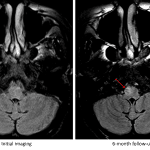

Initial MRI

- Relatively symmetric, minimally expansile T2/FLAIR signal hyperintensity in the midbrain and pons (predominantly involving the corticospinal and central tegmental tracts with sparing of the transverse pontine fibers) extending superiorly into the right greater than left internal capsules. There is also involvement of the left superior cerebellar peduncle

- No corresponding enhancement, restricted diffusion, or susceptibility artifact

6 month follow-up MRI

- Overall improved appearance and extent of T2/FLAIR signal hyperintensity in the brainstem extending into the internal capsules

- New expansile T2 signal hyperintensity in the right ventral medulla

- No corresponding enhancement, restricted diffusion, or susceptibility artifact

Hypertrophic olivary degeneration (HOD)